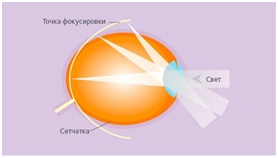

Схема традиционной коррекции миопии:

Часть света в периферической зоне уходит за сетчатку, то есть возникает периферический гиперметропический дефокус.

При ношении ребёнком обычных линз, световой сигнал фокусируется перед сетчаткой и частично уходит в периферийную зону, которую специалисты называют «мнимым пространством».

В такой ситуации глазное яблоко рефлекторно реагирует на световые сигналы и слегка вытягивается за ними, удлиняется. При миопии это грозит увеличением «минуса» в диоптриях ваших линз.